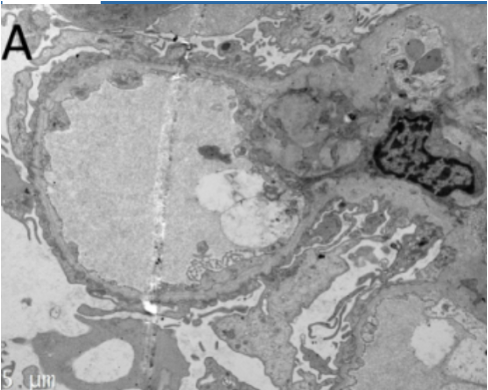

atheroembolic disease

A 77-year-old male presents to the office for follow-up after undergoing coronary angiography via femoral approach for stable angina 4 days ago. He feels well today and has no concerns. Past medical history reveals hypertension, hyperlipidemia, and type 2 diabetes mellitus. Vital signs and physical examination are normal. Laboratory studies reveal a blood urea nitrogen of 30 mg/dL (reference range: 6–20 mg/dL) and a serum creatinine of 2.7 mg/dL (reference range: 0.7–1.3 mg/dL). Prior to catheterization, his serum creatinine was 1.0 mg/dL. A renal biopsy is obtained, as shown in the exhibit.

The most likely cause of this patient's acute kidney injury is